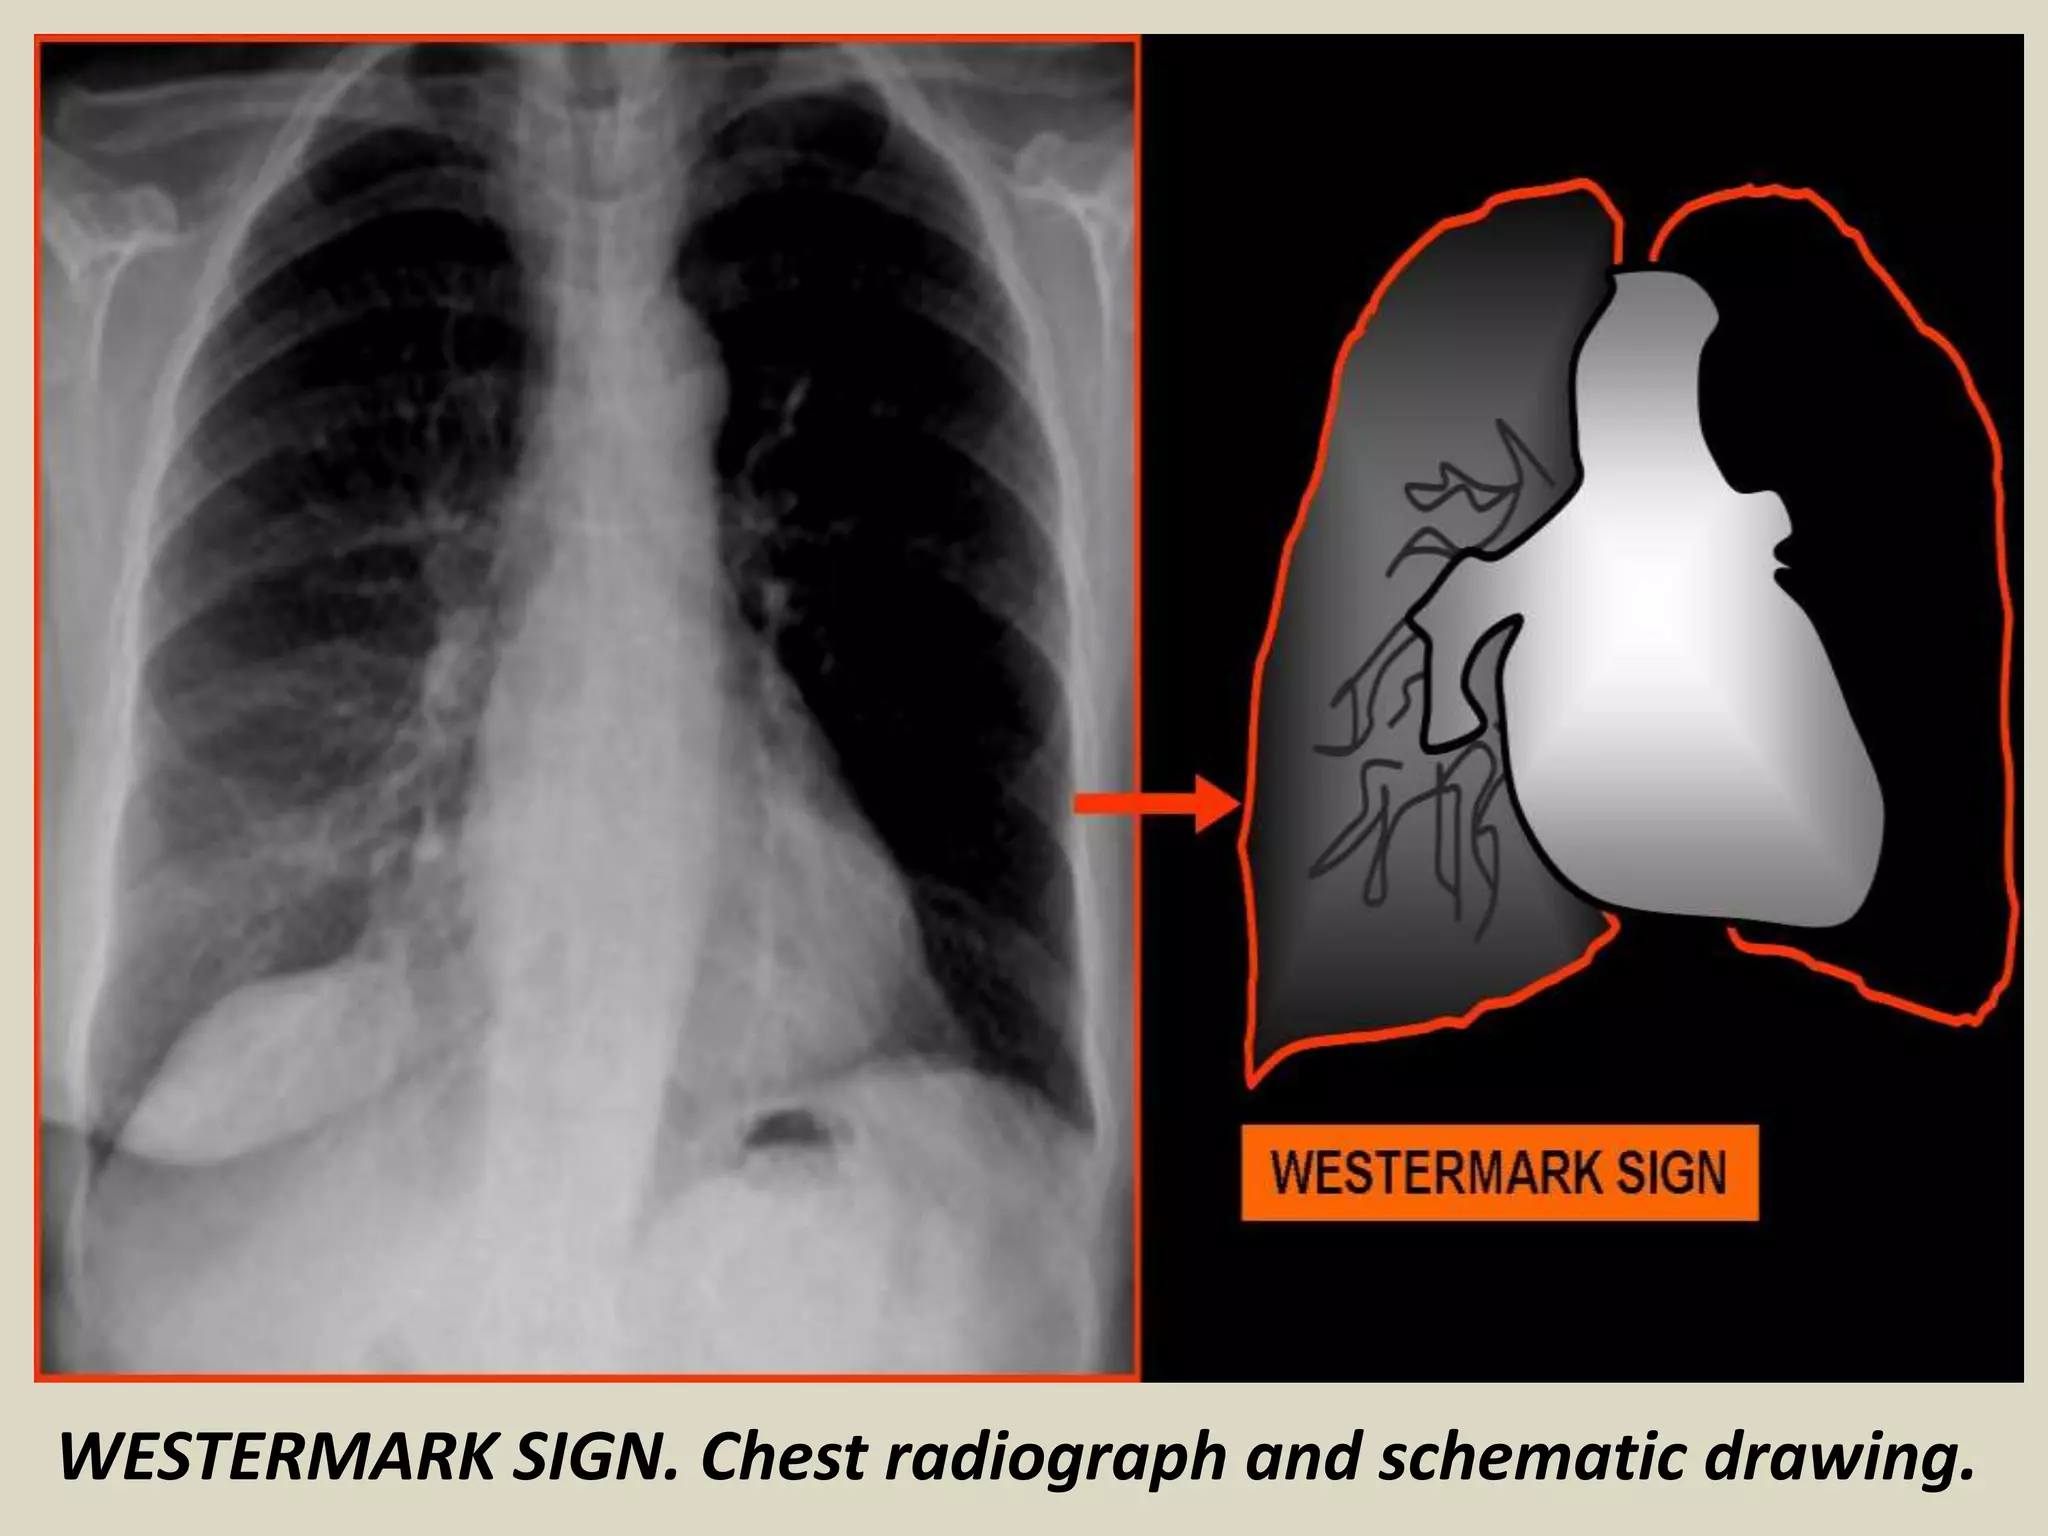

WESTERMARK SIGN

Described by Neil Westermarck in 1938

Chest radiograph and CT show increased lucency or

hypoattenuation

Typically signifies either occlusion of a larger

lobar/segmental artery or widespread small vessel

occlusion

Represents oligemia distal to PE; seen only in 2% of

patients

Sign results from combination of dilatation

pulmonary arteries proximal embolus and collapse

of distal vasculature

Low sensitivity 11%, high specificity 92%

WESTERMARK SIGN. Chest radiograph and schematic drawing.

Westermark Sign.